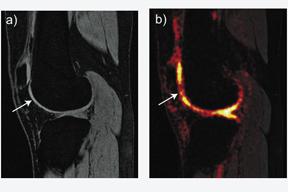

A technique dubbed sodium MRI may help diagnose osteoarthritis in knee joints years before the condition fully develops. While traditional MRI works by exciting hydrogen protons in the body, this technique focuses on a structural material in cartilage, glysosaminoglycan, which occurs in a complex with sodium. Sodium has its own set of excitation and relaxation frequencies and is more restricted to cartilage than water is. Since the element is far less common to the body than hydrogen is, using this scanning technique has generally produced inferior image quality, resolution and signal to noise.

Recent technological innovations have allowed clinicians to develop sodium MRI into a viable clinical scan, according to Gary Gold, M.D., associate professor of radiology at Stanford School of Medicine.

“We thought if we took a new MRI sequence with 3D imaging and short echo times developed by electrical engineers at Stanford, and combined it with a high-quality coil and a 3T scanner, we might be able to get the kind of image resolution that we really need to see cartilage,” said Dr. Gold.

Dr. Gold and other clinicians at Stanford have imaged about 17 patients who tore their anterior cruciate ligament (ACL) in the past 10 years in order to see differences in sodium signals between a patient’s injured knee and a healthy knee.

In all cases so far, there has been significant loss of glysosaminoglycan found in the sodium MRI scans within three years of an ACL injury, potentially allowing for accelerated diagnosis.